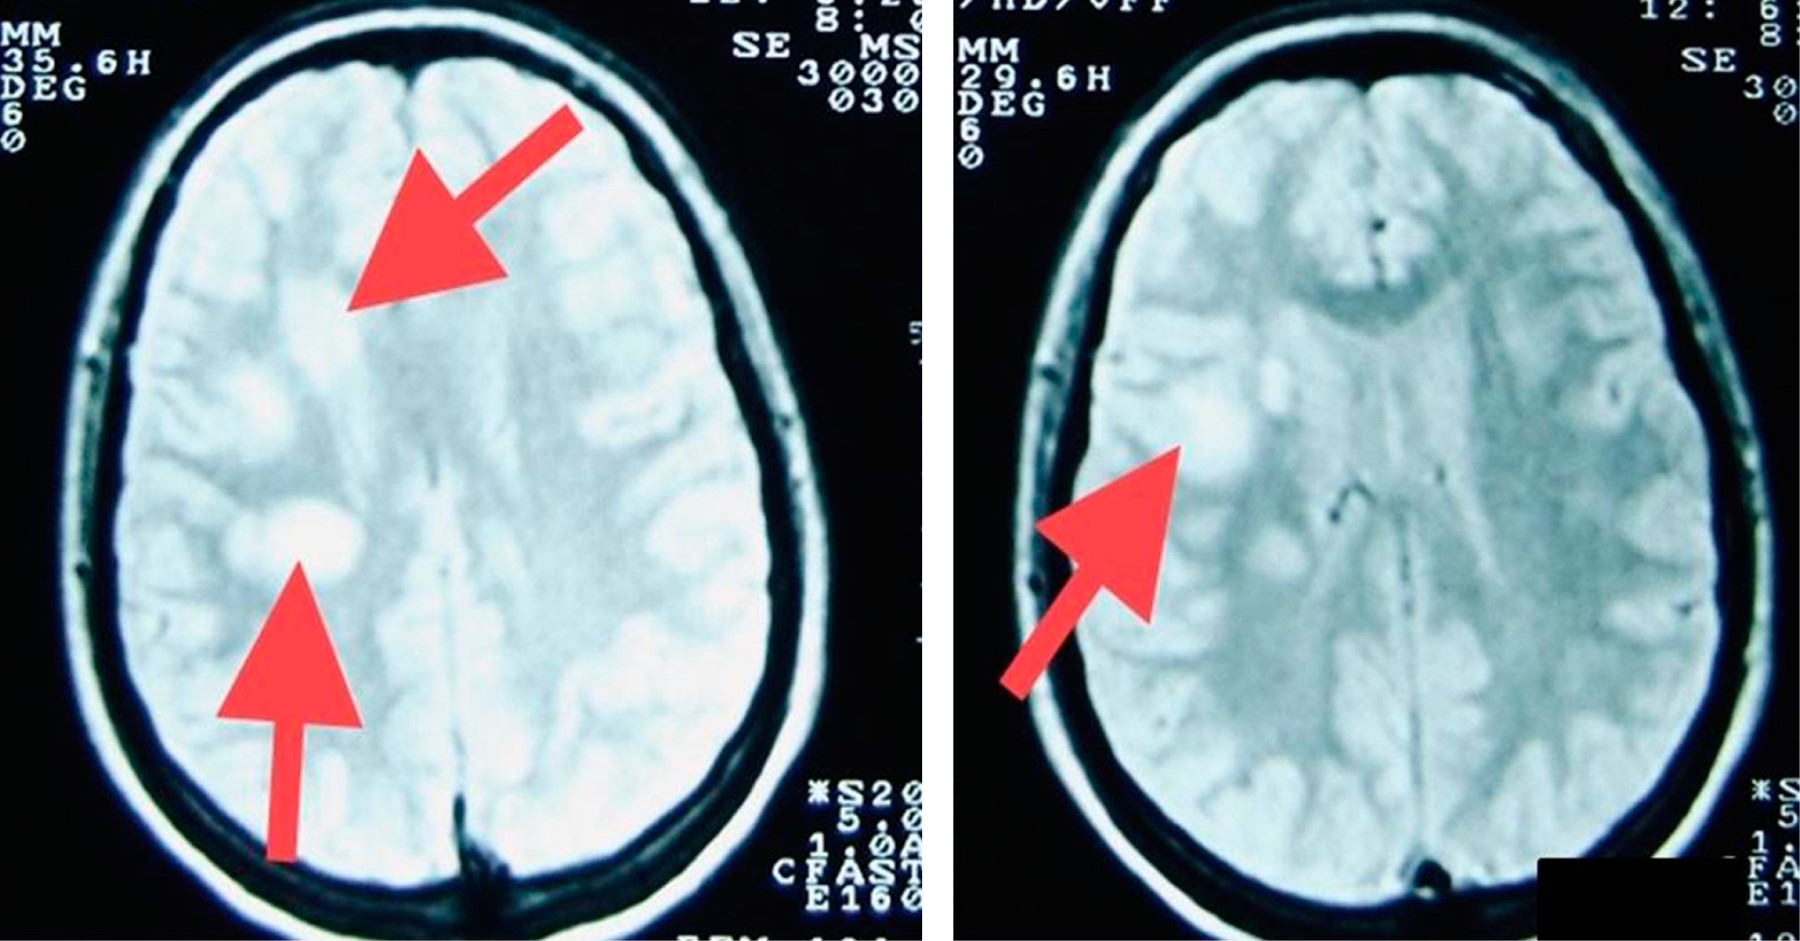

Objective: We describe two adolescent patients with multiple sclerosis, which is a demyelinating disease of the central nervous system. Presentation of the cases: The first case was a 14-year-old female patient with overweight; her condition was characterized by dizziness, headache, paresthesia in the lower limbs, diplopia and bradylalia. On physical examination, compatible data of cerebellar involvement were identified. A magnetic resonance imaging (MRI) of the skull showed areas of demyelination in the posterior fossa. Multiple sclerosis, the relapsing-remitting variety, is diagnosed. After the administration of steroids and beta interferon, there was improvement in symptoms. Second case: 13-year-old female, who presented fall from her own height, bladder incontinence, loss of strength in the left arm and leg. On physical examination, left hemiparesis was detected. MRI: demyelination data in lateral ventricle, cerebellum and spinal cord. The patient improved after starting steroids and interferon. Conclusions: The clinical presentation of multiple sclerosis in pediatric patients is a challenge, since it is a condition with unspecific manifestations. Establishing the diagnosis requires multiple studies. The earlier treatment is started, the more favorable the prognosis.

Figure 2

Figure 3